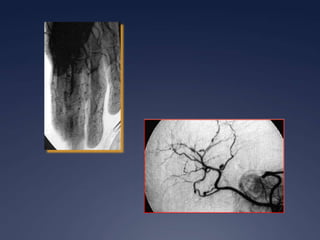

Périartérite noueuse

 Vasculite nécrosante segmentaire avec des

lésions d’âges différents

 Inflammation périvasculaire avec nécrose

fibrinoïde

 Formation de micro-anévrisme

 Atteinte rénale

 Sténose et anévrisme dans les artères rénales

 Biopsie

 Inflammation périvasculaire

 Nécrose fibrinoïde de la média

 Atteinte de l’endothelium

 Puis fibrose…

 Musculaire permet diagnostic dans 60 %

 Rénale déconseillée